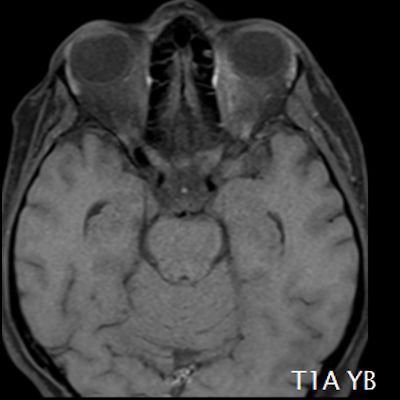

- (A) Torakal MRG’de sagital görüntülerde üst-orta torakal düzeyde T2A hiperintens (oklar), T1A izo-hipointens (ok) uzun segment ekspansil sinyal değişikliği izlenmekte olup sagital postkontrast T1A’da kontrast tutulumu mevcuttur (oklar). Bulgular longitudinal ekstensif transvers miyelit (LETM) ile uyumludur.

- (B) Orbita MRG’de aksiyel yağ baskılı T1A’da optik sinir prekiazmatik segmenti (oklar) gösterilmiş olup sırası ile aksiyel ve koronal post-kontrast yağ baskılı T1A görüntülerde bilateral optik sinir prekiazmatik segmentte kontrast tutulumu dikkati çekmektedir (oklar ve daire).

- Optik nörit varlığında özellikle optik kiazma ve posterior optik sinir tutulumu görülür ve bilateral olabilir.

- Transvers miyelit sıklıkla santral gri cevheri etkileyen ve üç veya daha fazla vertebral gövde uzunluğunu etkilemektedir (LETM).

- Kontrast madde enjeksiyonu sonrasında neredeyse tüm akut NMO lezyonları, yamalı, düzensiz veya periferik olarak kontrastlanma gösterir.